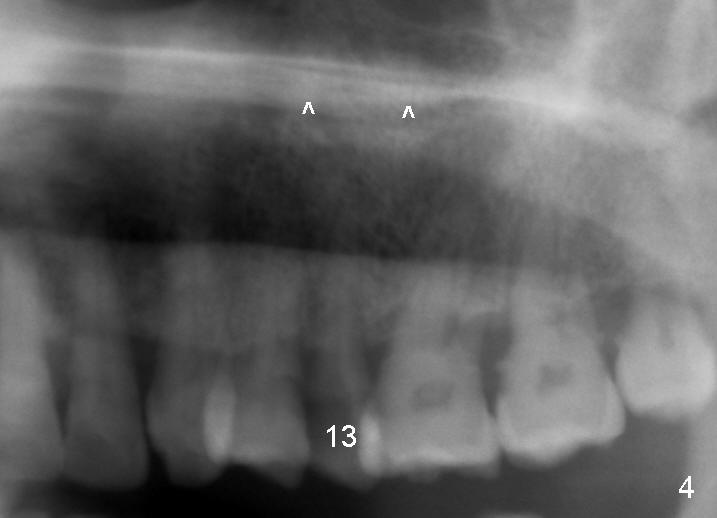

A 57-year-old man has history of chronic periodontitis (Fig.1,2, taken 9 and 7 years ago, respectively). Last April the tooth #13 had crown fracture (Fig.3). He returned to clinic for scaling & root planing last week (Fig.4). Fig.3,4 show long root and bone. Arrowheads in Fig.4 indicate the sinus floor.

If the buccolingual (B-L) width of the extracted root is much wider than the mesiodistal (M-D) one, a D1 (4 (B-L) x 3.5 (M-D) cervical) or D2 (5.5x3.5) implant will be selected (20 mm long). To reduce tapping and vibration, 1.5 mm pilot drill and 2.5 mm reamer will be used to start osteotomy at 20 mm deep, 3 mm reamer at 17 mm if needed, followed by D osteotomes. Save autogenous bone for grafting buccally later.

The root of the extracted tooth is not so similar to the D implant. So a tapered implant is placed.